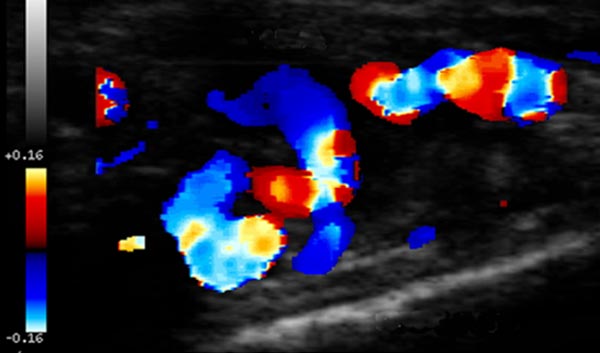

Die farbkodierte Duplexsonographie zeigt eine massive Mehrdurchblutung, jedoch nicht in multiplen, sehr kleinen netzartigen Gefäßen wie in einem infantilen Hämangiom zu erwarten, sondern in eher etwas größeren Gefäßen. Dieser Befund ist eher mit einer arteriovenösen Malformation vereinbar.